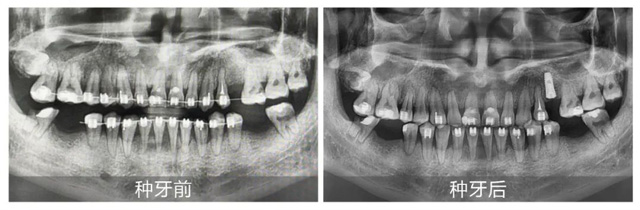

刘先生术前术后全景片对比